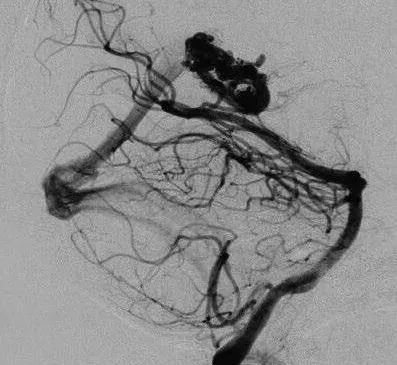

他紧急行半侧颅骨切除术,随后血管造影显示右侧动脉瘤,AVM由双侧PcaA供血,引流向前MedFrV和SplenV【左侧ICA像,(a)前后位(b)侧位】(c)首先通过双侧开颅并排夹闭动脉瘤(鼻朝右,中线呈水平,重力牵开右侧额叶),然后切开动脉瘤使之缩小。